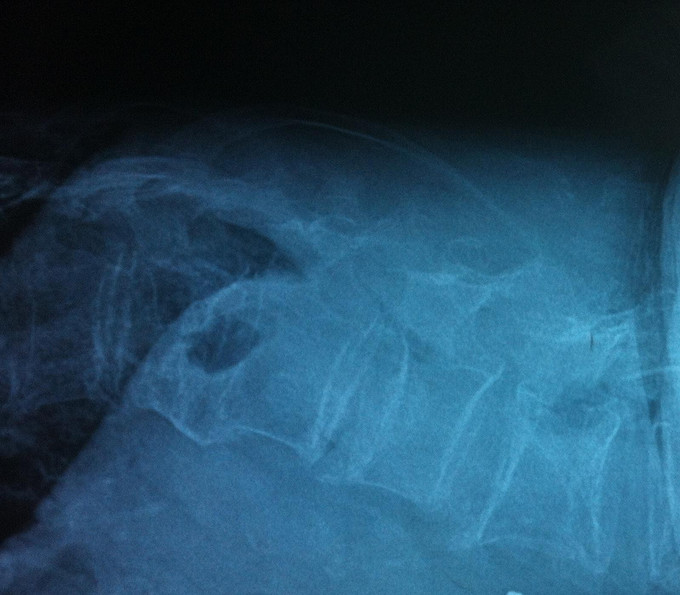

查体:腰部活动受限,腰骶部叩痛明显,体位试验阳性,双下肢感觉无减退,双侧屈髋、伸膝、踝背伸、踇背伸、跖屈肌肌力4-5级,双侧膝腱反射++,跟腱反射+,双侧巴氏征阴性。 辅助检查: X-ray:骨质疏松,腰3、5楔形变,MR:骨质疏松,腰3、5新鲜骨折